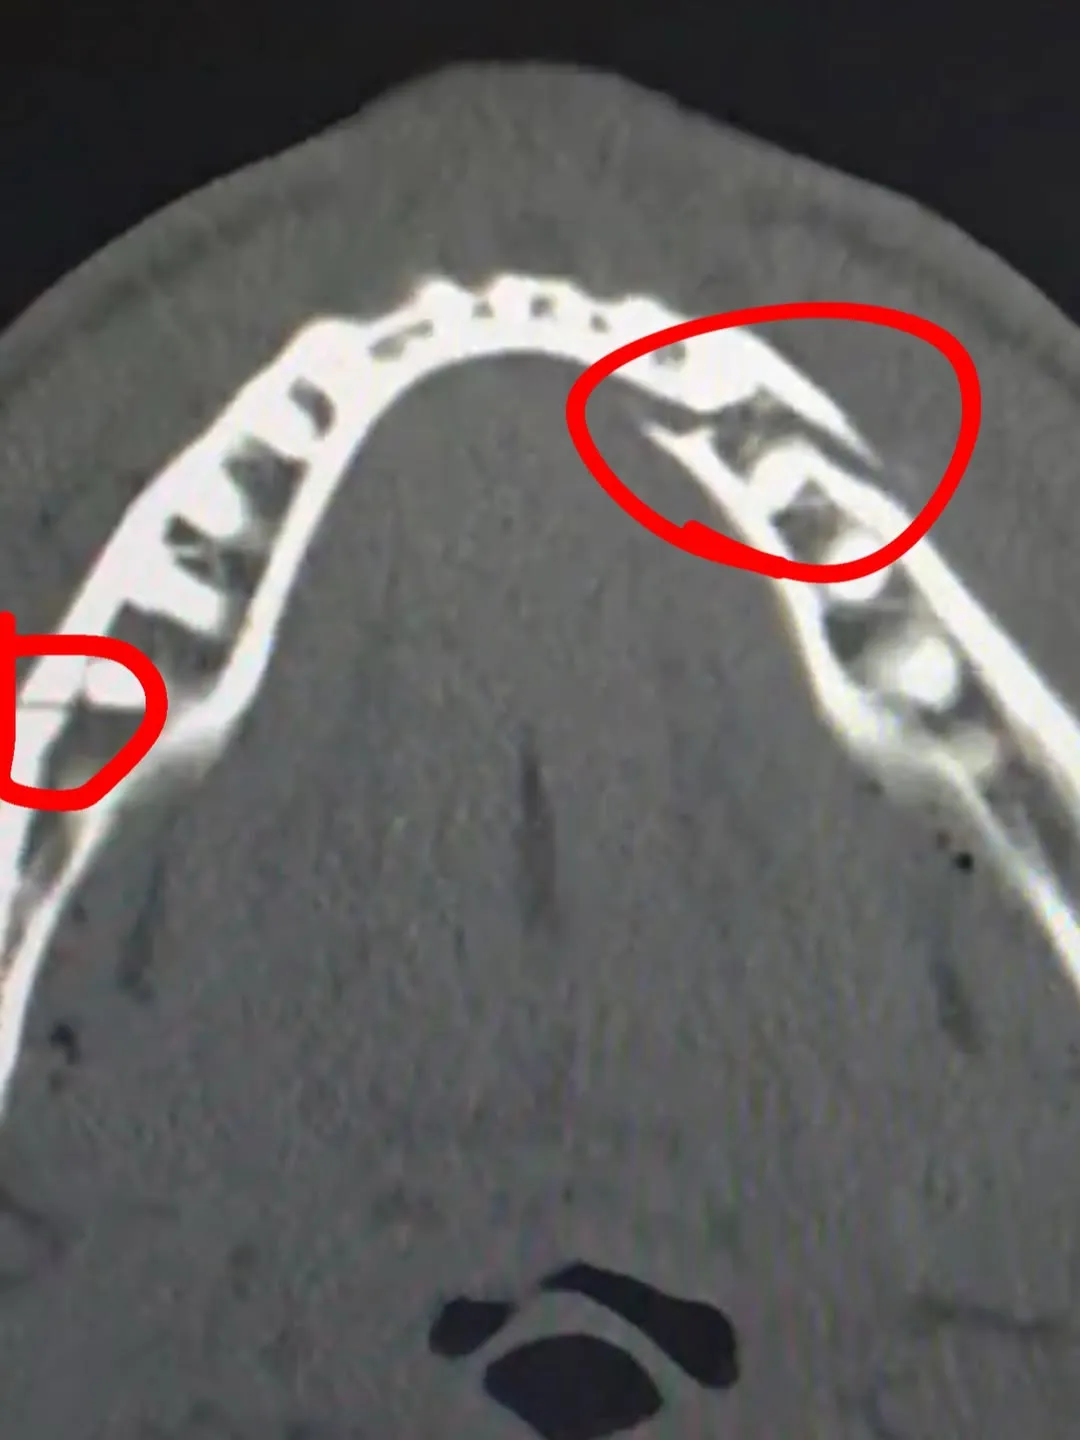

Jake Paul reveló que sufrió una doble fractura de mandíbula

El youtuber reveló que sufrió una doble fractura de mandíbula en la pelea, aunque no mostró ningún recelo para con Joshua y mostró que a pesar de la derrota mantiene su humor característico. “Denme a Canelo [Álvarez] en diez días“, comentó.

Anthony Joshua le fracturó la mandíbulo a Jake Paul.

- El boxeador Jake Paul reveló que sufrió una doble fractura de mandíbula tras el combate.